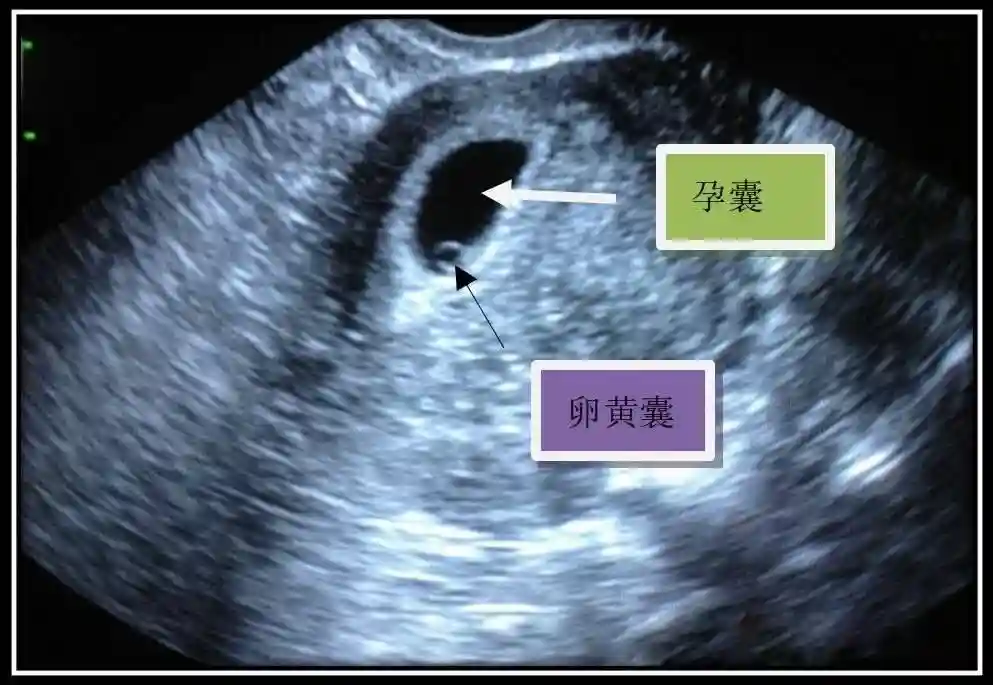

2️⃣卵黄囊:是妊娠囊内第一个解剖结构,直径<7mm。表现为小环状,中央为无回声,囊壁薄,内透声好。卵黄囊位于胚胎旁胚外体腔内。卵黄囊通常在孕5-6周时出现,5-10周稳步增长,一般不超过7mm,至12周消失。妊娠囊的大小与卵黄囊之间有一定关系,妊娠囊平均直径> 8 mm 时,经阴道超声均应显示卵黄囊,妊娠囊平均直径> 18 mm 时,经腹超声均应显示卵黄囊。